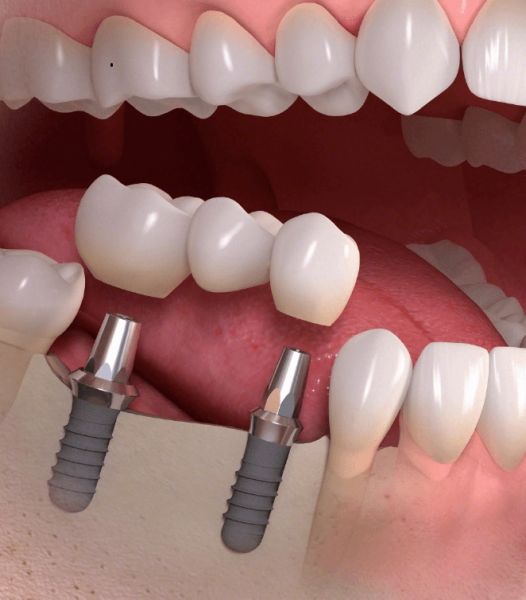

Diş implantları ağızda eksik olan dişlerin yerine konması amacıyla, genellikle titanyum veya titanyum bileşiklerinden hazırlanan yapay diş kökleridir.

Titanyum vücut dokuları ile etkileşime girmediği ve kuvvetlere karşı dirençli bir materyal olduğu için implant malzemesi olarak tercih edilir. İmplantlar daha önceden kaybedilmiş dişlerin oluşturduğu boşluklara ya da ciddi bir enfeksiyon yoksa hemen çekim sonrası diş yuvasına yerleştirilebilir.

İmplant uygulamasının asıl amacı, üzerine kullanılabilir dişler yapmaktır.

İmplantlar, sabit ya da hareketli protezler yapmak amacı ile kemiğin yeterli ve uygun olduğu durumlarda basit bir operasyonla çene kemiğine yerleştirilirler. Eğer kemik miktarı ve yoğunluğu istenilen seviyede değilse implant uygulamasından önce kemik oluşturmaya yönelik işlemler yapılması gerekebilir.